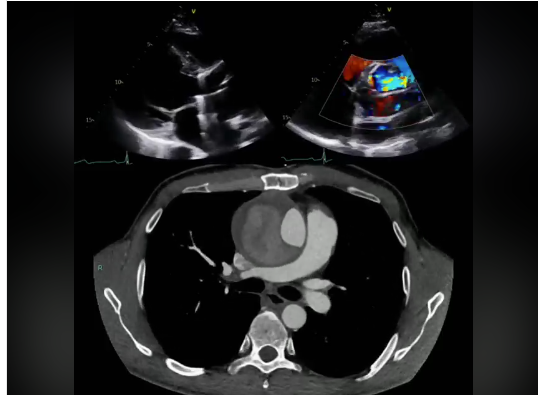

Cardiopathie hypertensive ou cardiomyopathie hypertrophique ? youtu.be/S_0nOAakMuU?si… via @YouTube

#echocardiography #Cardiovascular #echofirst #HeartDisease #HeartFailure #cvImaging #cardiology #CVD #cardiotwitter #cardiology #EACVI2023